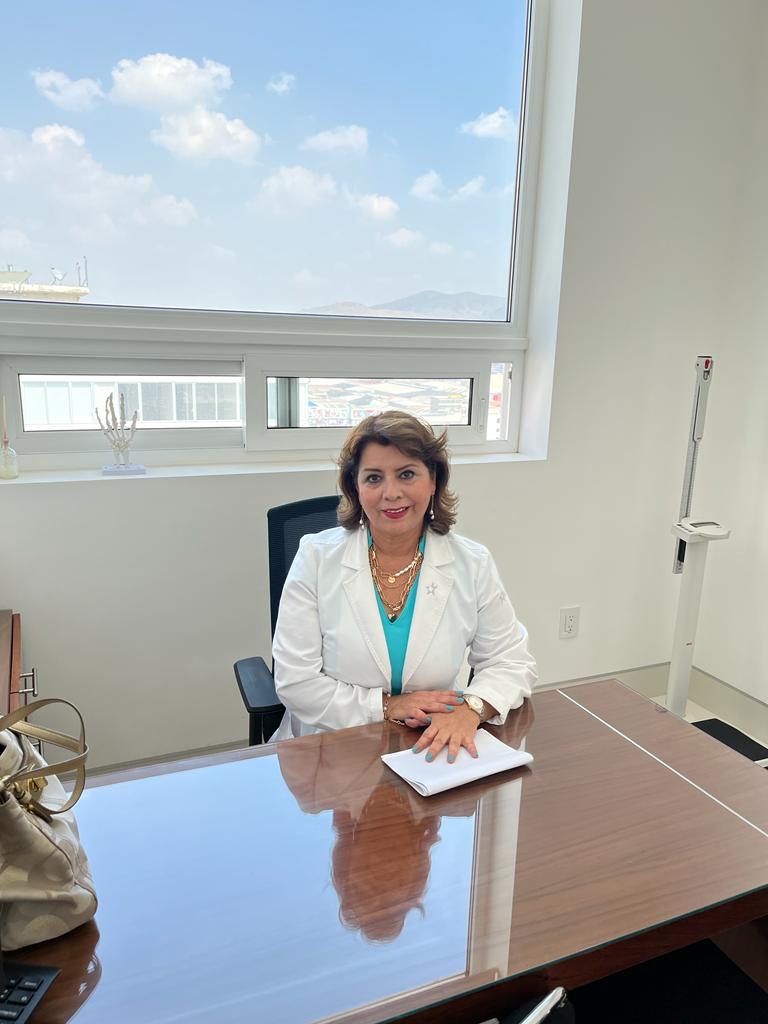

La Clínica Neumológica del Dra. Alma Rosa Ortiz es un centro de excelencia en diagnóstico y tratamiento de enfermedades pulmonares. Su equipo especializado y tecnología avanzada garantizan atención personalizada y terapias innovadoras. El compromiso del doctor y su vocación elevan la salud respiratoria de sus pacientes, siendo un referente en la capital. Gran labor eleva la fe y esperanza.

La certificación del Dra. Alma Rosa Ortiz Aguirre garantiza una atención neumológica de alta calidad, basada en los más altos estándares médicos. Su experiencia en el diagnóstico y tratamiento de enfermedades respiratorias como asma, EPOC y fibrosis pulmonar permite ofrecer soluciones precisas y efectivas. Con un enfoque integral, brinda atención especializada para mejorar la salud pulmonar y la calidad de vida de sus pacientes.